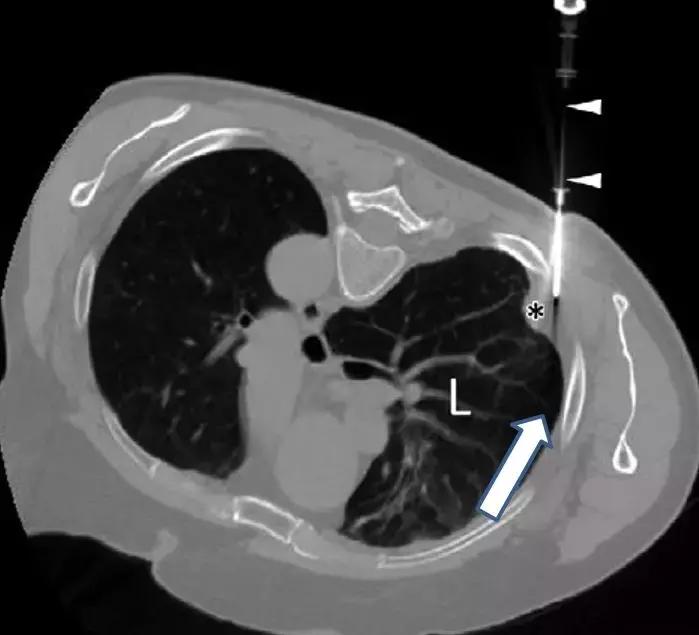

三、彩超引导下胸膜活检

超声指引下,切割活检针达到目标部位后扣动弹簧扳机完成活检,所以特异性和敏感性都不错。

这是在彩超引导下的胸膜活检,胸水较少,胸膜局灶增厚。在穿刺中,可以看到针的所在位置。

优点:实时引导、无射线暴露、费用相对较低。

缺点:依赖超声仪器品质,因为不同的机器达到的效果不同;另外,由于超声扫描的Total的放置角度、位置都对成像有影响,所以超声医师的经验也很重要。